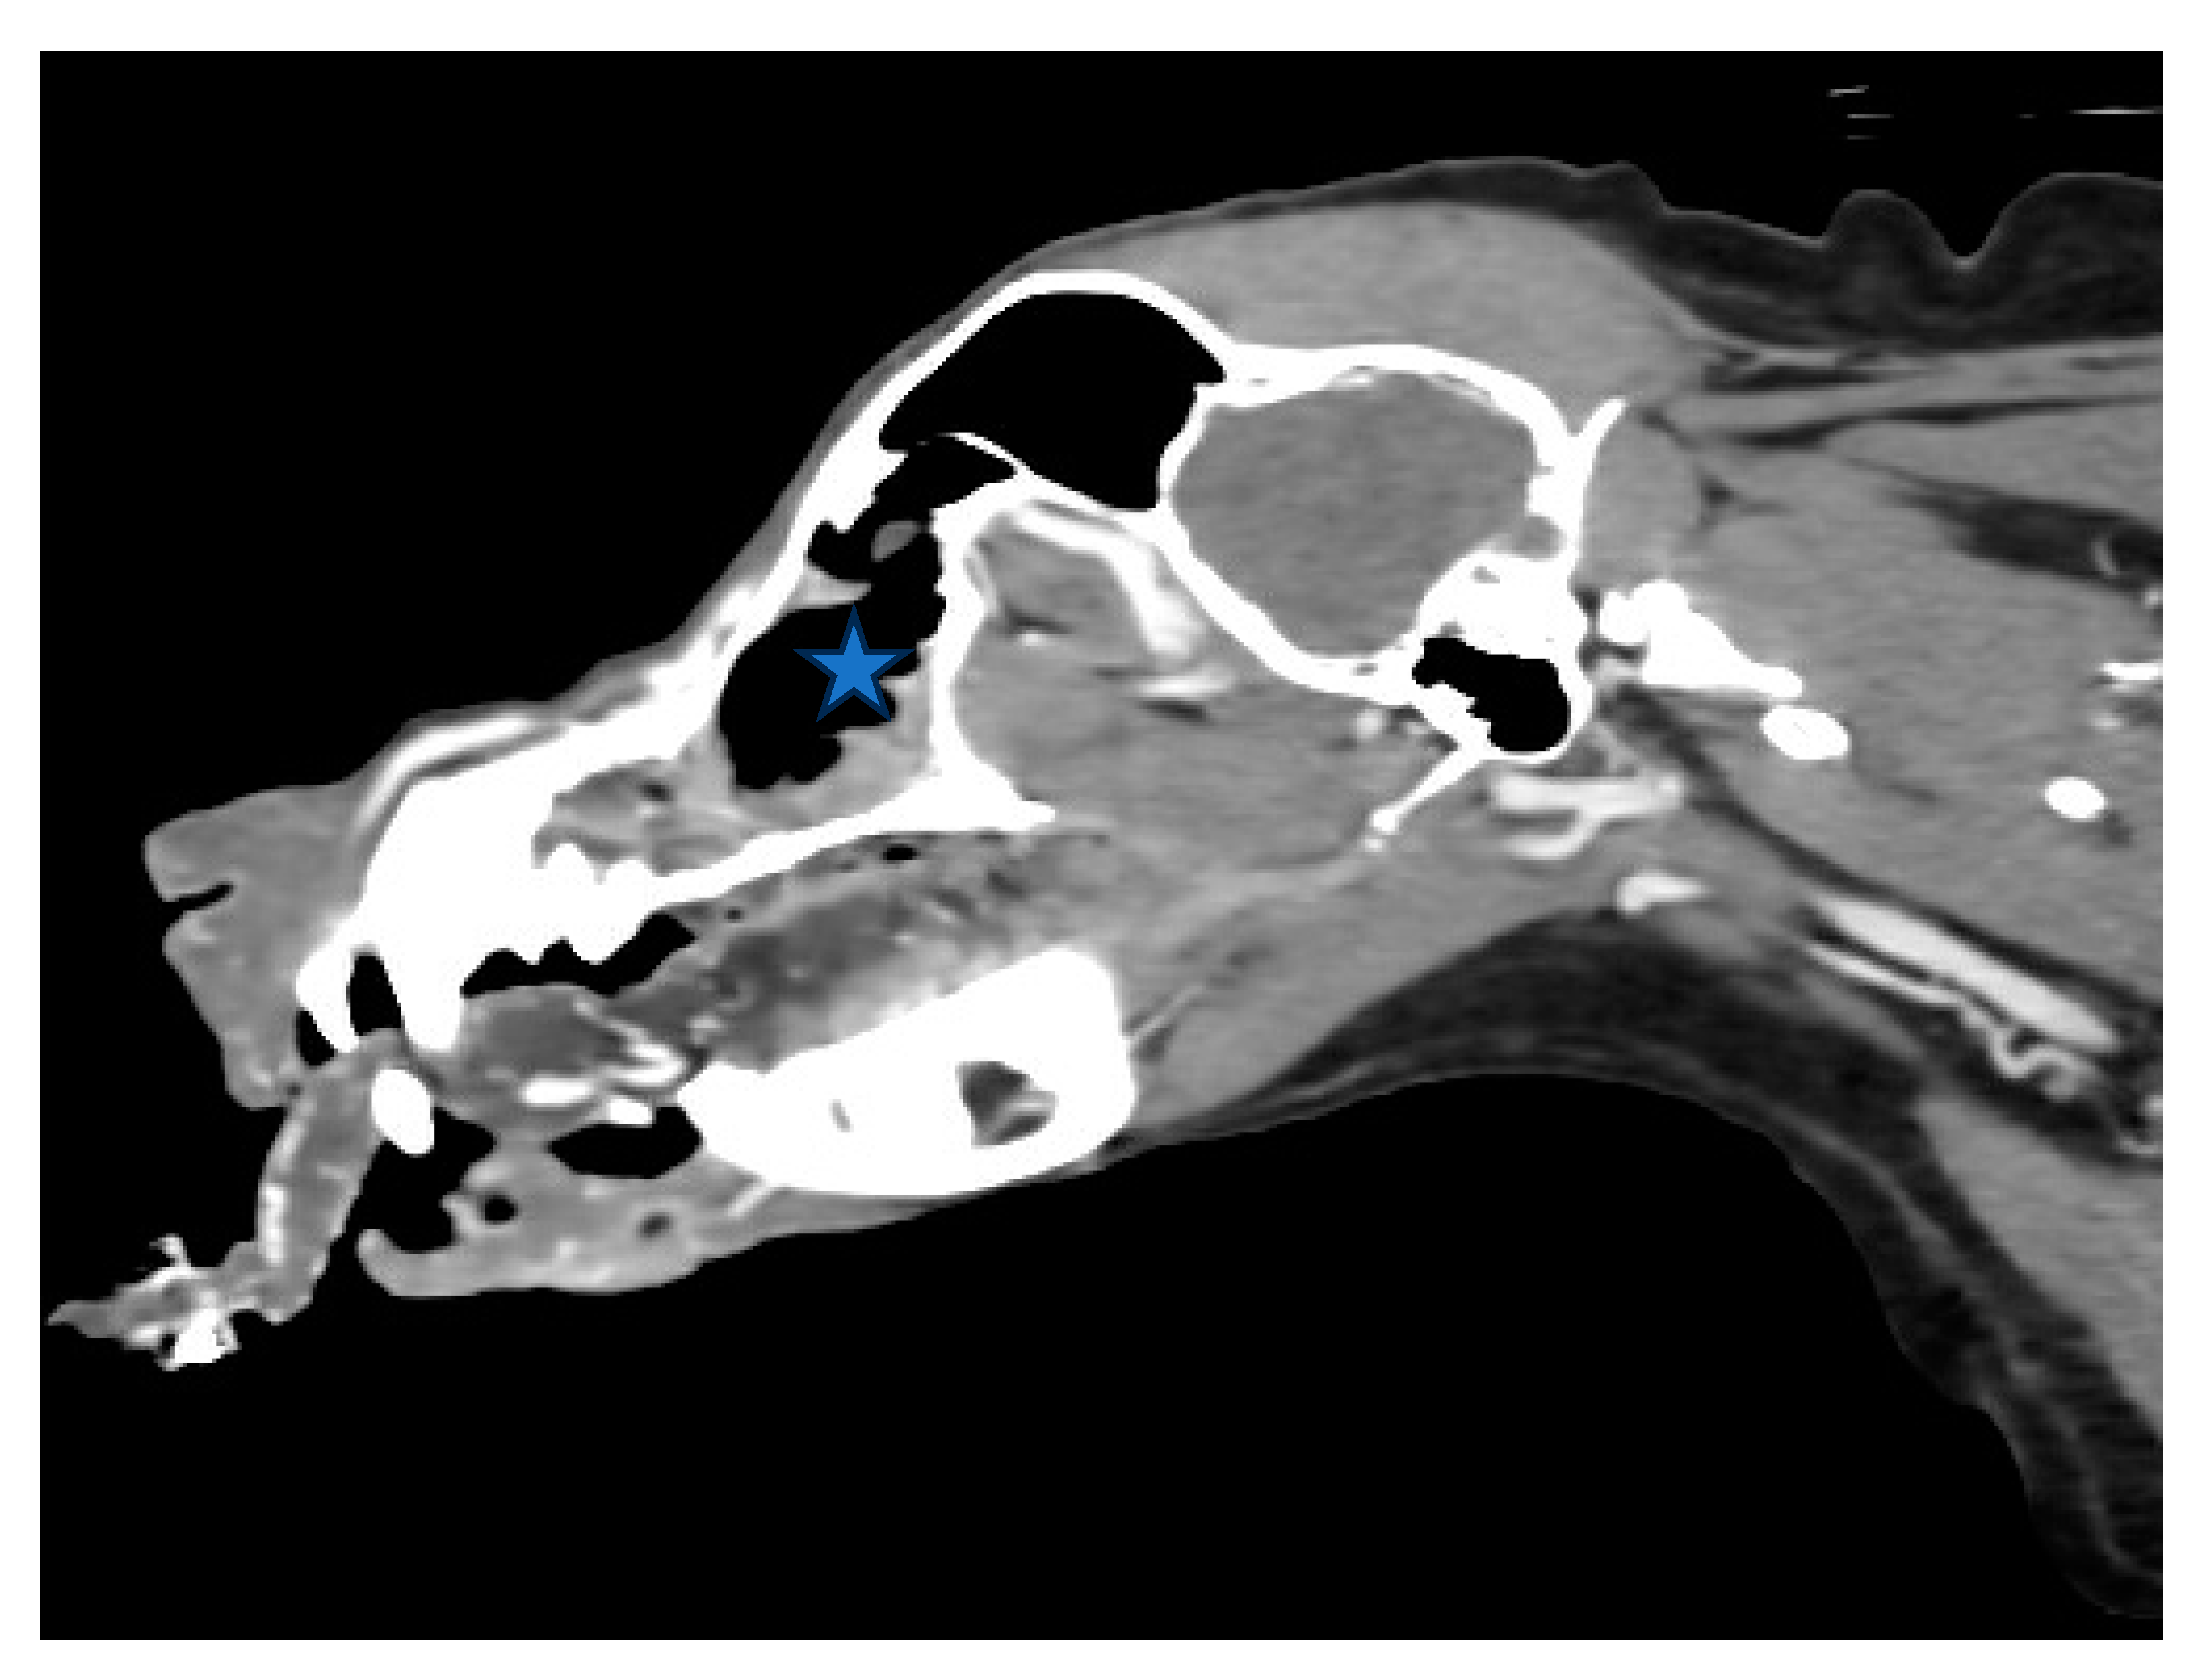

Figure 3. (A,B). Sagittal view of CT scan of skull. The size of the nasal tumor decreased significantly (Asteroid).